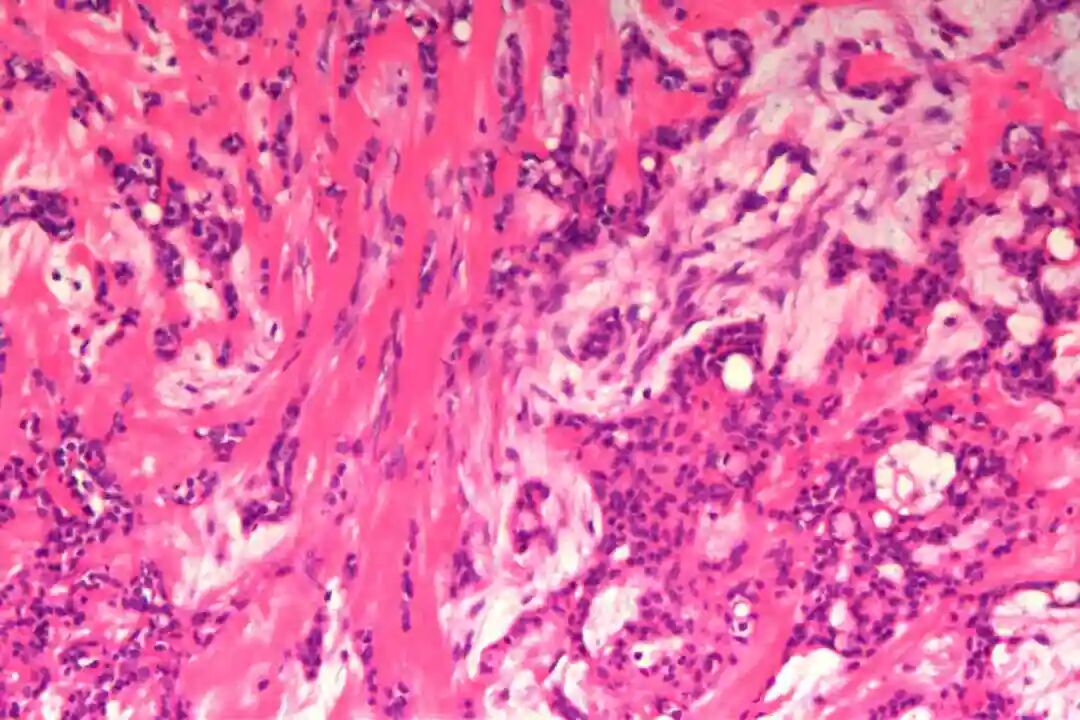

细胞形态:基底样肌上皮细胞体积较小,呈圆形或卵圆形,细胞核深染、染色质均匀,核仁不明显,胞质稀少、淡嗜酸性;腺上皮细胞体积略大,呈柱状或立方状,细胞核淡染、染色质疏松,核仁清晰,胞质丰富、嗜酸性。实性巢团内可见少量微小腔隙,腔隙内可含有少量嗜酸性或嗜碱性黏液样物质(PAS染色阳性),这是实体型与其他实性肿瘤的重要鉴别点;核分裂象少见,一般≤5个/10HPF,部分实体型区域可出现轻度至中度细胞异型性,但无明显恶性增殖活性表现,与高级别乳腺癌的细胞异型性有明显区别。

实体型区域与经典型区域无明显明确界限,相互穿插分布,实体型巢团可逐渐过渡为经典型的筛状或管状结构,两种区域的细胞成分相互延续,均可见腺上皮细胞与肌上皮细胞的混合存在,无明显细胞异型性差异(实体型区域异型性略高于经典型,但整体温和)。这种混合性形态是本病的重要镜下特点,也是与单纯实体型PACC、单纯经典型PACC的主要区别。